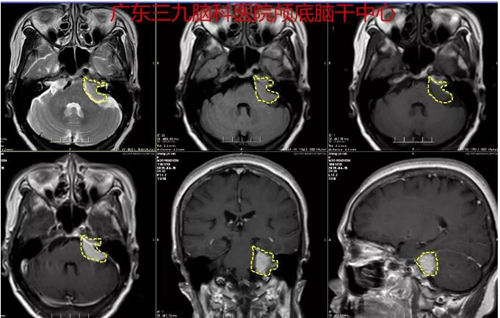

图2:术前MR示左侧桥小脑角区占位病变并向邻近内听道蔓延,考虑脑膜瘤可能性大,不除外神经鞘瘤;2.左侧基底节区及右侧小脑半球陈旧梗塞灶;右侧丘脑陈旧出血灶可能性大;3.脑白质多发变性灶;脑桥可疑缺血灶;4.幕上轻度脑皮质萎缩;5.MRV示左侧横窦、左侧乙状窦细小,上矢状窦额部细小显示不清,均考虑发育因素。